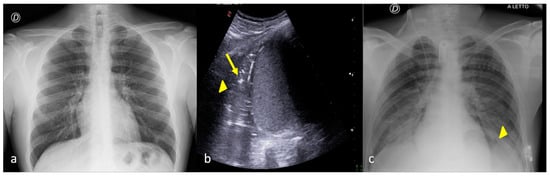

4. Checking and Monitoring the Devices

2. Characterizing and Monitoring Areas of Decreased Transparency on the CXR